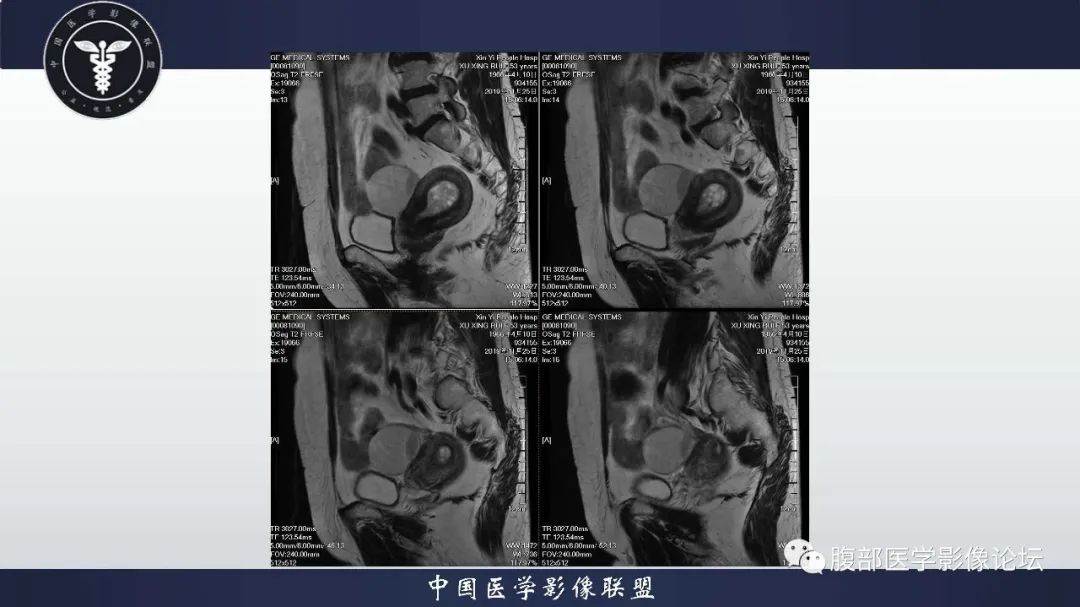

子宫内膜息肉1例MR影像